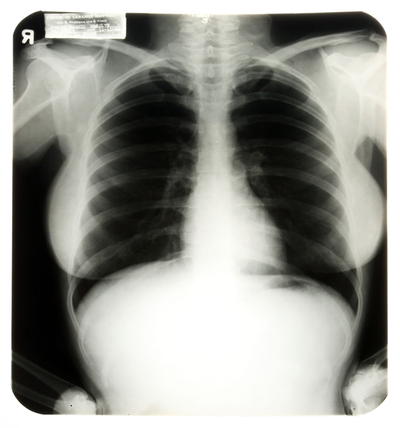

Casi 36.600 euros recaudaron tres radiografías del pecho de Marilyn Monroe que la actriz se hizo en el hospital Cedars of Lebanon, en Florida, en noviembre de 1954, seis años antes de su muerte. A pesar de que los organizadores de la subasta en el Planet Hollywood Resort de Las Vegas no esperaban recibir más de 2.000 euros, un admirador lo suficientemente rico logró hacerse con la imagen interior de la estrella.

Las radiografías le fueron realizadas a la actriz tras ser admitida en el hospital para someterse a una cirugía por endometriosis, una enfermedad del útero que le causaba unos dolores insoportables. En la época de la operación, Monroe estaba aún con su segundo marido, el jugador de béisbol Joe Di Maggio, por lo que las placas llevan su nombre de casada, Marilyn Di Maggio.